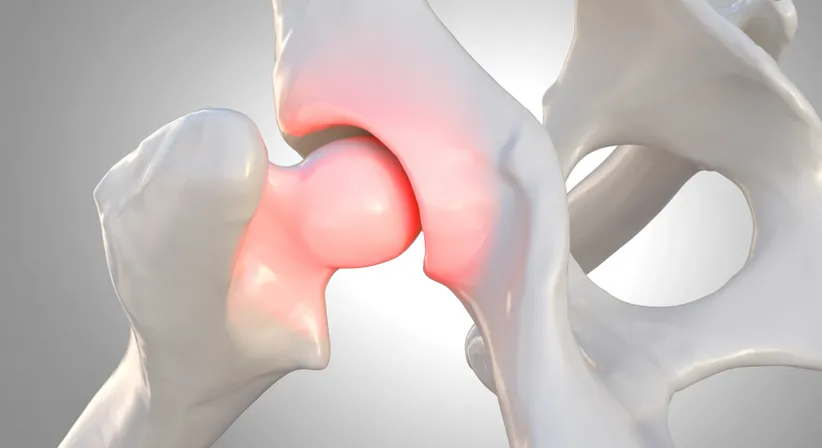

Die Hüftdysplasie des Jugendlichen und Erwachsenen ist durch die in Österreich durch Prof. Reinhard Graf entwickelte Säuglingssonografie glücklicherweise deutlich zurückgegangen. Früher war sie eine der häufigsten Ursachen für den frühzeitigen Verschleiß des Hüftgelenks und dann infolge der Notwendigkeit des frühen Einsetzens eines künstlichen Hüftgelenks.

Dadurch, dass die Hüftdysplasie heutzutage seltener vorkommt, wird sie leider auch häufig zu spät erkannt und auch zu spät therapiert. Wenn man jedoch eine Hüftdysplasie rechtzeitig beim Jugendlichen oder Erwachsenen erkennt, kann man die dadurch in jungen Jahren auftretende Arthrose mit einer minimal invasiven Korrekturoperation verhindern oder deutlich hinausschieben.